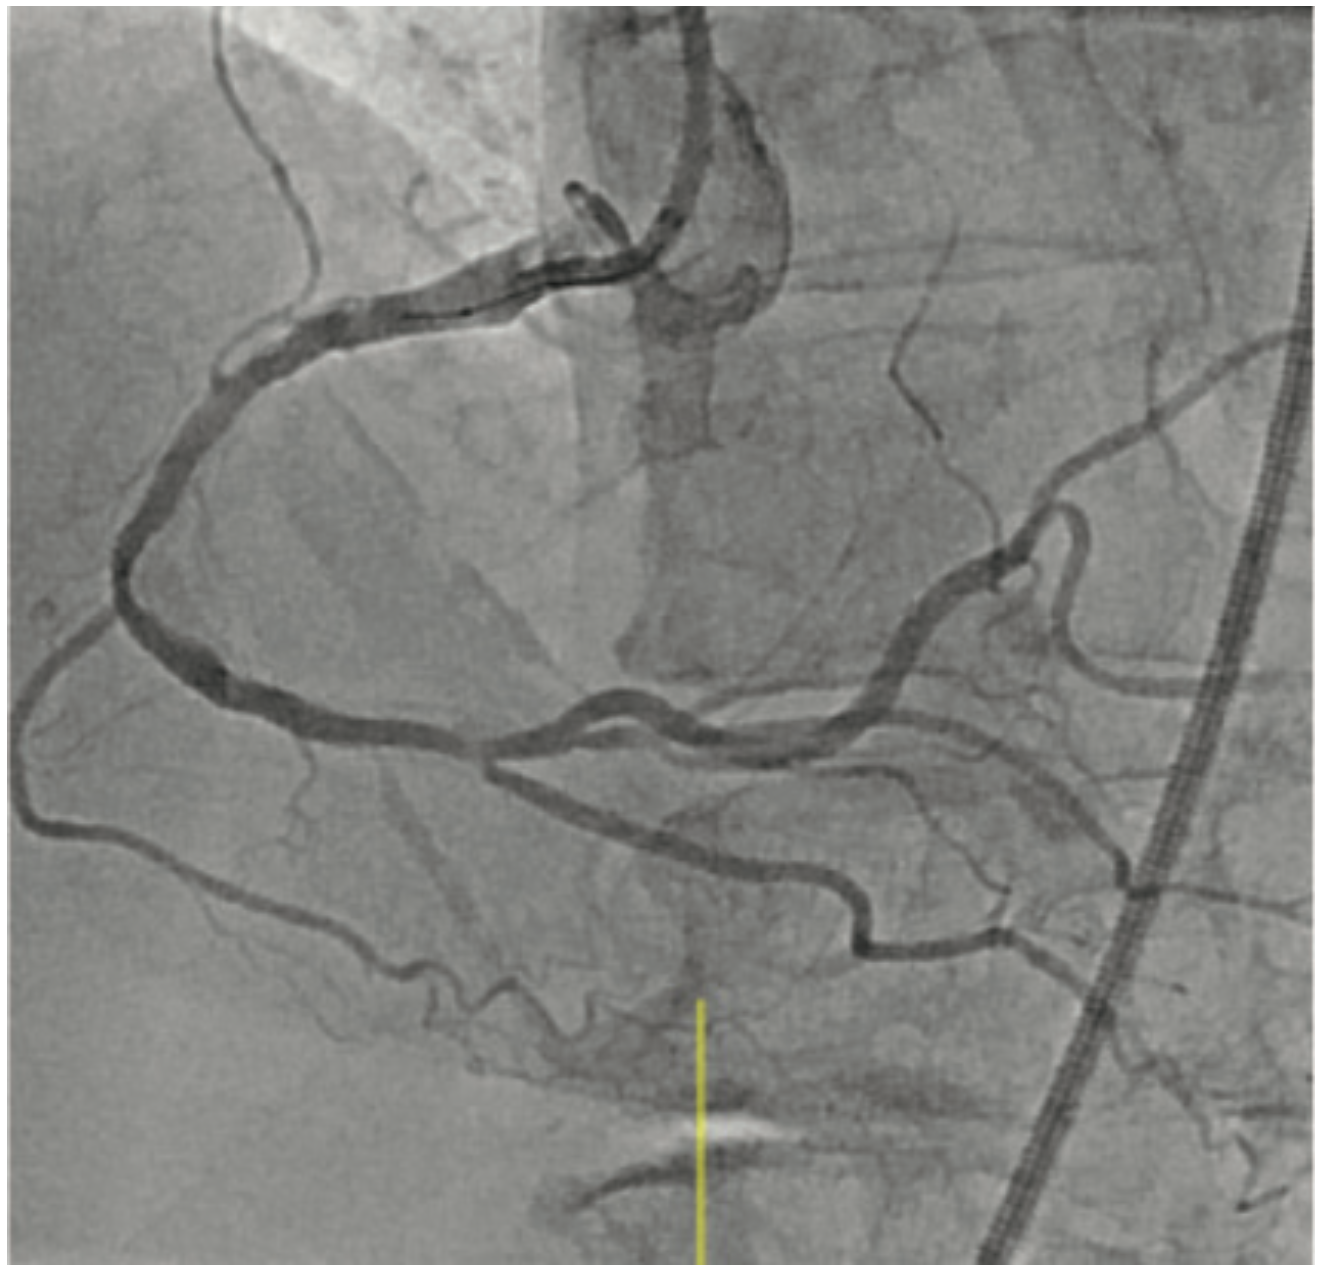

Intravascular lithotripsy (IVL) has been shown to be both safe and effective in the treatment of calcified coronary artery disease, with low rates of device-related adverse events, as shown in the DISRUPT CAD study series.3-6 Certainly, any device that may assuage operator concerns regarding complications when treating complex lesions could translate to an increase in use of calcium modification where indicated. Since we know that inadequate lesion preparation may lead to higher rates of in-stent restenosis and stent thrombosis, it follows that IVL could help lower suboptimal PCI rates in both men and women.

Small retrospective studies have suggested that women may be at an increased risk for procedural complications after atherectomy. Procedural complications are often related to vascular injury during plaque modification. As post-menopausal women have been shown to have increased arterial stiffness, less vessel compliance, and increased vascular fragility, it is not surprising that these factors, in conjunction with smaller coronary artery size, could lead to higher rates of coronary perforation and dissection during treatment of calcified plaque. The sex-specific analysis of the DISRUPT CAD series of studies presented at SCAI 2022 demonstrated that there was no difference in angiographic complications, successful stent delivery, and 30-day adverse cardiovascular events between men and women.7 These are certainly reassuring data, which suggest that the possible safety signals seen in women treated with atherectomy may not be present with IVL.

First, it is important to note that the single-arm design of the DISRUPT CAD studies does not allow for comparisons of IVL with other calcium modification techniques and additionally, only 23% of patients in these studies were female. As such, it is difficult to say that we have definitive data that IVL will improve outcomes in female PCI patients with calcified lesion(s). That being said, I do believe that the DISRUPT CAD safety data could lead to an uptick in IVL use in female patients in particular, which could certainly contribute to not only lower rates of procedural complications, but also to the performance of more optimal PCI in female patients, with resulting better long-term clinical outcomes.